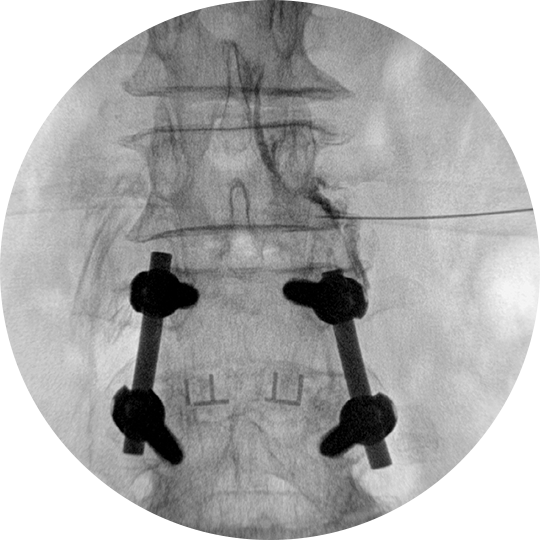

C-arm 영상장치를 보면서 신경손상의 위험성을 줄인 스프링장치가 내장된 도관을 통증의 원인이 되는 부위에 위치시킵니다.

그 후 염증을 완화시키는 약물, 척수와 척추관의 유착을 분리하는 히알우로니다제 분해 효소 또는 고장성 식염수 등을 경막외강에 주입시켜 염증을 없애고 유착을 제거합니다.